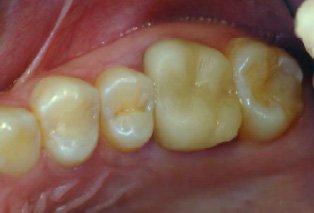

これらの銀歯と土台を除去してみると、内部が黒く変色していることが確認できました。変色部分と金属の被せ物を丁寧に除去し、金属を使用しない被せ物に置き換えました。

その結果、患者様からは、これまで感じていた複数の症状が改善したとの報告がありました。ただし、こうした症状の改善には個人差があり、すべての方に同様の効果があるとは限りません。